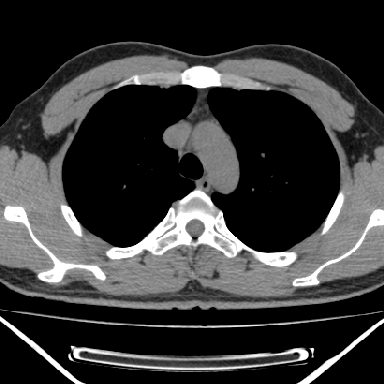

m 30 右胸痛10年

右上后纵隔脊柱旁类圆形肿块,边界光整,与胸腔呈钝角,首先考虑来源于肺外,神经源性肿瘤(神经鞘瘤可能大,神经鞘瘤)

右上后纵隔旁软组织肿块影,与肺界面光滑,与胸壁呈钝角相交,提示肺外病变。位于肋骨下缘,边缘清楚,呈三角样指向与右侧椎间孔,但并示进入椎间孔;与对侧神经根对比,属同一走行方向。

考虑后纵膈良性肿瘤,神经源性肿瘤可能大。

鉴别:胸膜来源肿瘤。影像表现虽有肺外征象,但无胸水等相应佐证;再者,病史前10年,超长,与胸膜肿瘤不太吻合。

右上后纵隔脊柱旁类圆形肿块,边界光整,与胸腔呈钝角,首先考虑来源于纵膈,神经源性肿瘤可能大。

右上后纵隔脊柱旁见长椭圆形肿块,边界光整,与胸壁呈钝角。周围骨质未见异常。

考虑、1、后纵隔神经源性肿瘤;

2、不除外单发胸膜间皮瘤。